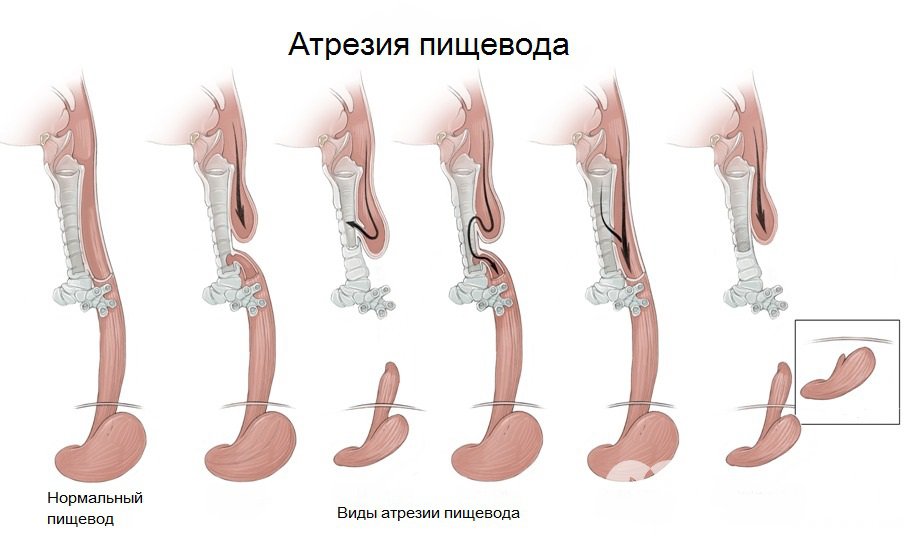

Виды атрезии пищевода

Виды атрезии пищеводаАтрезия пищевода встречается с частотой от 1 до 4 случаев на 1000 новорожденных (с одинаковой частотой у детей обоих полов). Нередко она сочетается с другими аномалиями развития, такими как:

Атрезия пищевода бывает двух форм:

- Свищевая. Характеризуется наличием сообщения между трахеей и пищеводом (трахеопищеводного свища).

- Изолированная. При ней трахея и пищевод не сообщаются между собой.

Значительно чаще встречаются свищевые формы атрезии пищевода, которые, в свою очередь, бывают нескольких видов:

- свищевая атрезия трахеи и обоих концов пищевода;

- свищевая атрезия трахеи и проксимального отрезка пищевода;

- свищевая атрезия трахеи и дистального отрезка пищевода.

Иногда у ребенка наблюдается наличие трахеопищеводного свища, но без атрезии пищевода.

Самой тяжелой формой атрезии пищевода является аплазия, то есть полное его отсутствие.

Наиболее типичное место локализации атрезии пищевода – область бифуркации трахеи. Участок пищевода, который не соединяется с трахеей свищевым ходом, заканчивается слепо. Для изолированной формы заболевания характерно наличие двух слепо заканчивающихся участков пищевода, которые либо заходят друг за друга, либо соприкасаются между собой.